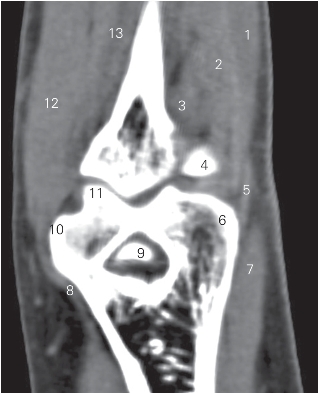

图4-31 经肘关节的冠状断层CT图像(软组织窗)

1 指伸肌 extensor digitorum 2 尺侧腕伸肌 extensor carpi ulnaris

3 肘肌 anconeus 4 桡骨头 head of radius

5 伸肌总腱 common extensor tendon 6 肱骨小头 capitulum of humerus

7 桡侧腕长伸肌 extensor digitorum 8 屈肌总腱 common flex tendon

9 鹰嘴 olecranon 10 内上髁 medial epicondyle

11 肱骨滑车trochlea of humerus 12 尺侧腕屈肌 flexor carpi ulnaris

13 指深屈肌 flexor digitorum profundus